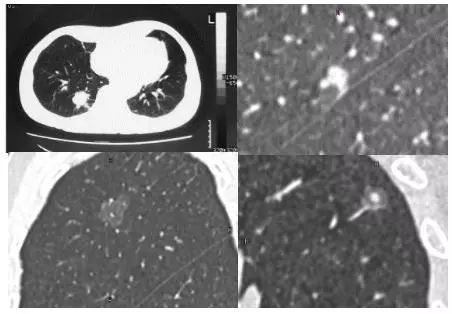

实性肺结节(solid nodule),间质血管都看不见(左上图),亚实性肺结节(subsolid nodule)包括纯磨玻璃结节(pure ground-class nodule,pGGN)(左下图),还有混杂性结节(mixed ground-glass nodule,mGGN),也称部分实性结节(part solid nodule),表现为间质样改变,中间实性,周围是磨玻璃样。

在2018年版的专家共识中,我们做了一个创新,首个共识提出大小分类:微小结节(直径<5mm),小结节(直径5-10 mm),肺结节(直径 30 mm以下)。这样分类有助于分级诊疗。